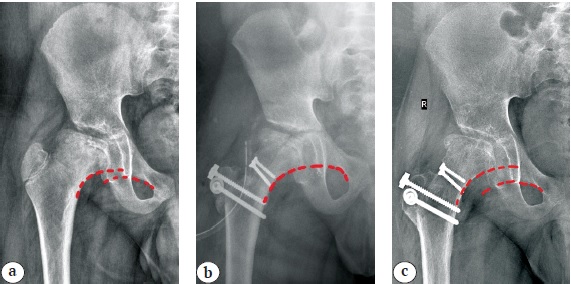

Радикальная хирургическая реконструкция привела к незначительному увеличению значений ШДУ по сравнению с дооперационными (p>0,05), чего нельзя сказать об остальных показателях. Так, произошло выраженное увеличение значений показателя ATD (p<0,05) за счет низведения большого вертела. Несмотря на выявленное прогрессирование деформации латерального края вертлужной впадины у части пациентов, показатель индекса ее сферичности оставался в пределах нормальных значений на протяжении всего срока наблюдения. Индекс сферичности головки бедренной кости претерпел значительные изменения после проведения хирургического лечения у всех пациентов, а его показатели стали находиться в пределах вариации физиологической нормы. Это привело к восстановлению не только конгруэнтности суставных поверхностей головки бедренной кости и вертлужной впадины, но и стабильности тазобедренного сустава в целом, о чем свидетельствуют показатели ICAS, FHEI, угла Wiberg и состояние линии Shenton непосредственно сразу после проведенной хирургической реконструкции. Вместе с тем на сроке наблюдения от 6 до 12 мес. у ряда пациентов, в основном с прогрессирующей деформацией латерального края вертлужной впадины, отмечалось уменьшение достигнутых интраоперационно значений угла Wiberg, увеличение процента экструзии головки бедренной кости из вертлужной впадины, а также нарушение непрерывности линии Shenton различной выраженности, что, на наш взгляд, является формирующимся вторичным подвывихом бедра и потребует необходимости проведения хирургической стабилизации тазобедренного сустава путем выполнения тройной остеотомии таза (рис. 6).

Рис. 6. Рентенограммы правого тазобедренного сустава (красной пунктирной линией отмечено состояние линии Shenton): a — до операции отмечается дисконгруэнтность суставных поверхностей головки бедренной кости и вертлужной впадины, умеренно выраженная деформация латерального края вертлужной впадины, разрыв линии Shenton, не превышающий величины 5 мм; b — непосредственно после проведения сегментарной резекции головки бедренной кости восстановлены конгруэнтность и стабильность тазобедренного сустава; c — через 8 мес. после операции отмечается формирование подвывиха бедра (прогрессирование деформации латерального края вертлужной впадины, разрыв линии Shenton более 5 мм)

Figure 6. Right hip X-rays (the red dashed line marks the condition of Shenton line): a — before surgery, incongruent articular surfaces of the femoral head and acetabulum, a moderate deformity of the lateral acetabular rim, and Shenton line disruption of a maximum of 5 mm are observed; b — immediately after femoral head reduction osteotomy, articular surfaces congruence and hip joint stability are restored; c — 8 months after surgery, the formation of hip subluxation (progressive lateral acetabular rim deformity, Shenton line disruption more than 5 mm) is observed

Необходимо отметить, что данная рентгеноанатомическая ситуация в подавляющем большинстве случаев отмечалась у пациентов с исходно имевшимся обратным вертикальным положением labrum acetabuli.